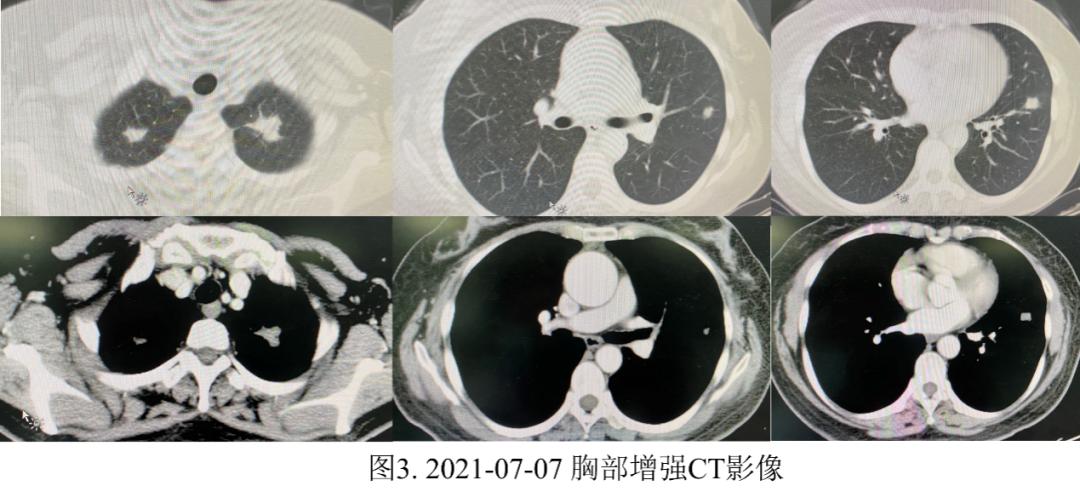

完善胸部增强CT:

排除禁忌后行CT引导下经皮肺穿刺活检术(图4),术后病理示:(左肺穿刺)送检为坏死组织伴出血,局灶查见少量慢性炎细胞成分,请结合临床(图5)。